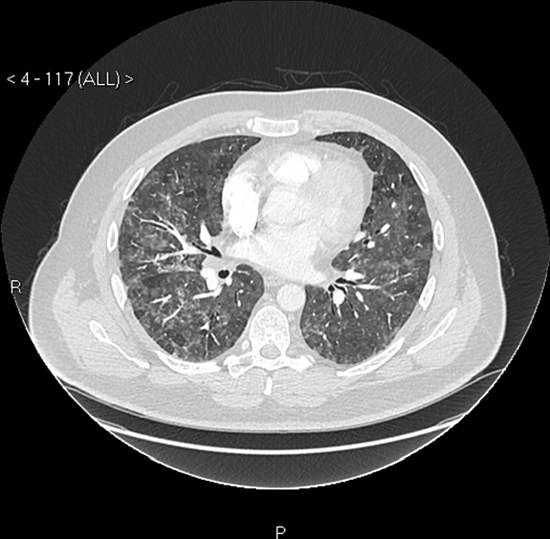

Kết quả chụp CT lồng ngực của Martin Taylor. Ảnh: BMJ